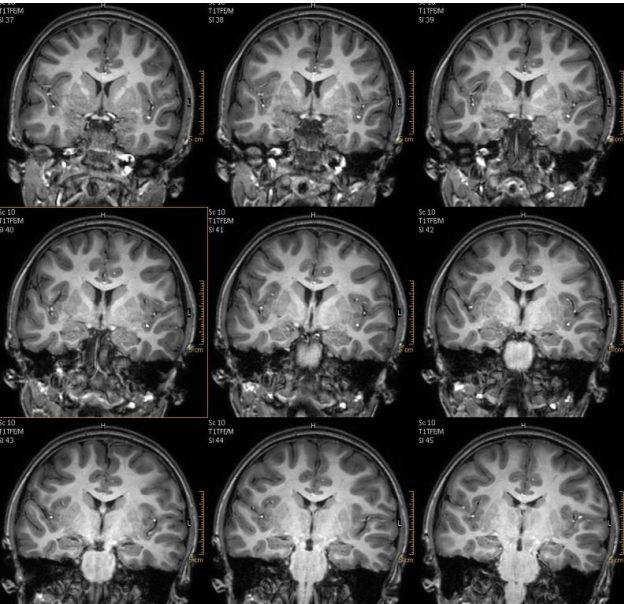

example of a T1 spoiled gradient echo sequence

SPGR Cor Oblique acquisition for a patient with history of seizures for evaluation of hippocampus